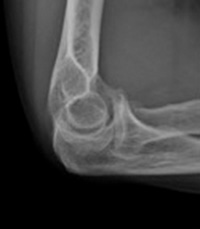

Ellenbogenarthrose

Die Diagnose wird durch die körperliche Untersuchung und durch Röntgenaufnahmen gestellt. In manchen Fällen ist ein CT oder MRT notwendig.